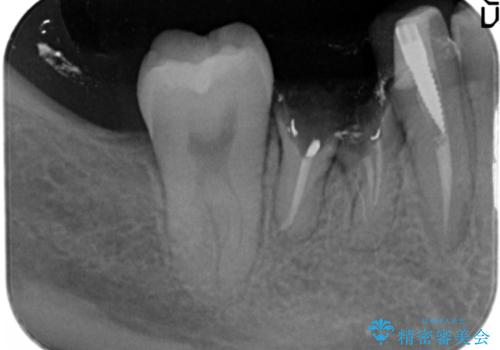

- 右下6番が保存不可能だったため、やむなく抜歯しました。

インプラント治療をご希望されたため、植立を行いました。